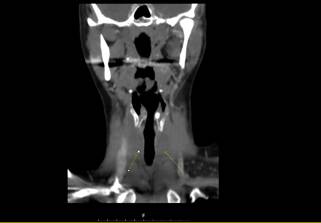

On CT scan bilateral mildly contrast-enhanced soft tissue density

masses were detected at the base of the neck coincident with thyroid anatomical

lobes location (Figures 1 and 2). Because differentiation of foreign body

Figure 2. Bilateral abscess cavities seen on coronal CT (Yellow arrows).